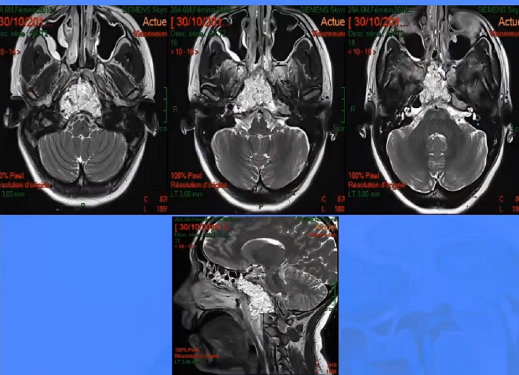

▼这是几年前做的一个手术,先把鼻中隔先推开,然后推开那些正常的组织,这里磨掉枕髁,暴露舌下神经管。虽然很具有挑战性,但是手术做得还是不错的,我们对病人进行了长期的随访,因为我们把所有的就是切开的软组织都复位了,所以看起来还可以,经过内固定以后,病人的颅颈交界区是很稳定的。

▼下图所示案例肿瘤看着很大,然后用30度、45度甚至70度的内镜,我们有很多带角度的器械,利用这些器械就可以切除肿瘤。可以先切开黏膜,然后把蝶窦内的黏膜推开,然后进入肿瘤。目前我们正在努力的开发这方面的器械,没有这些器械我们是做不了手术的。

▼这是术后的MRI,大家看到的高信号的是脂肪组织,我觉得利用内镜到达颅颈交界区更简单。